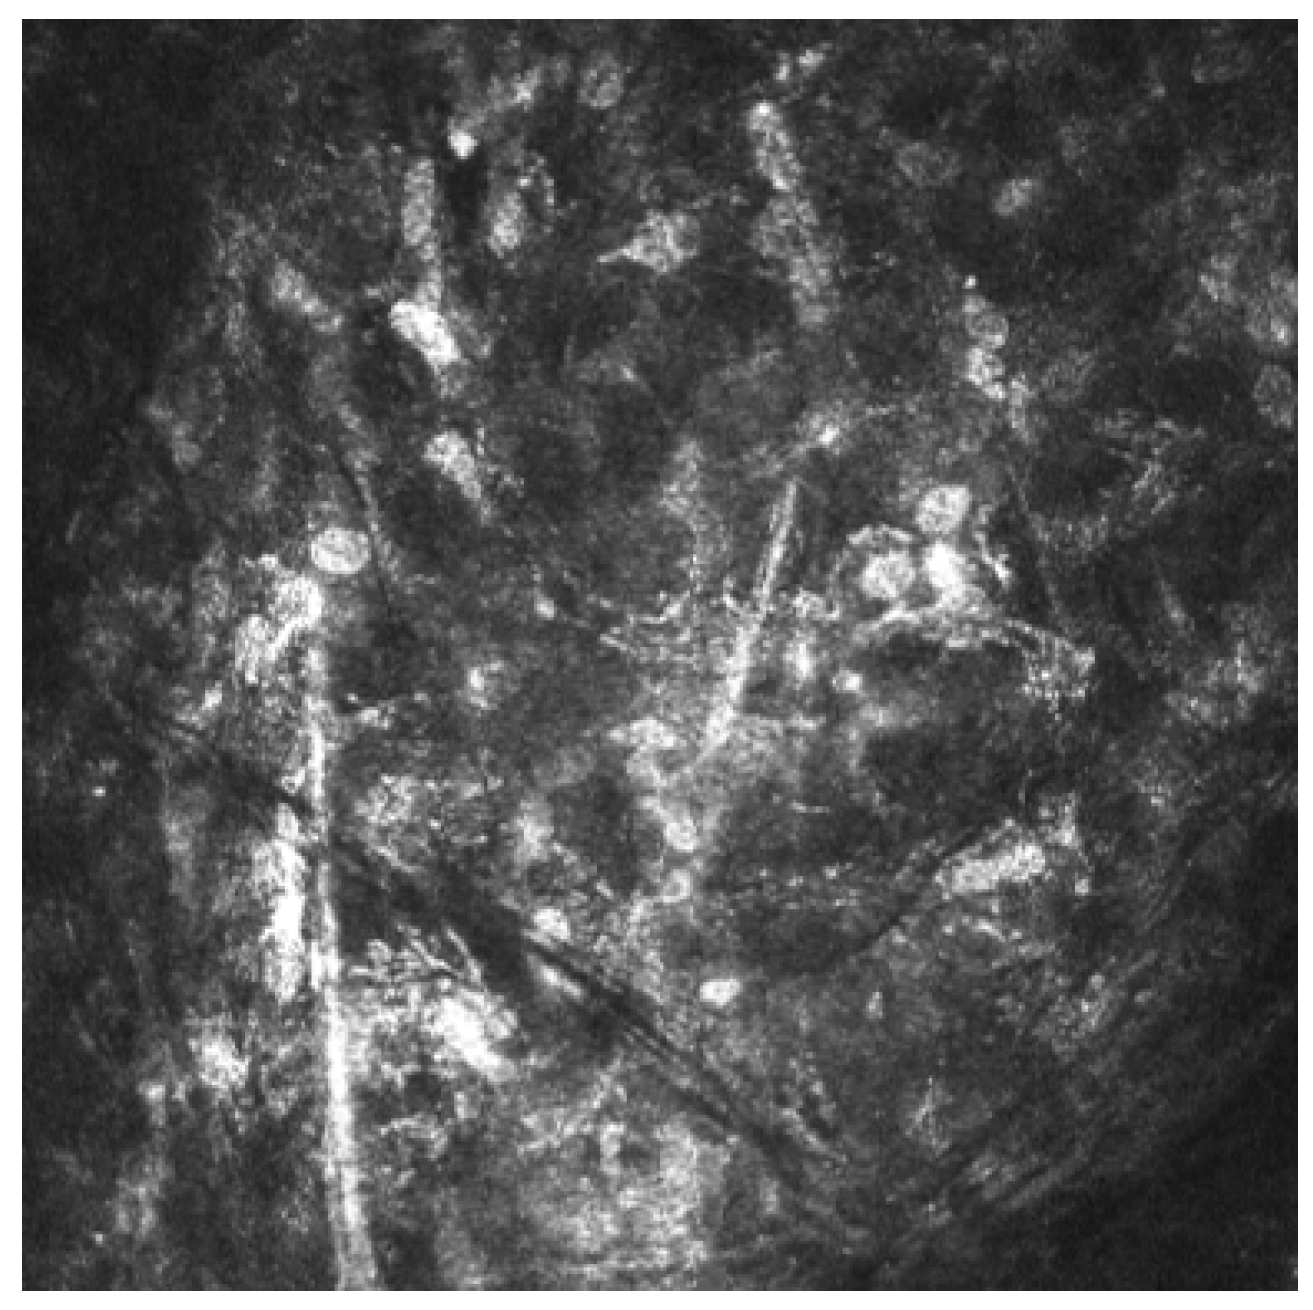

The diagnosis of AK is based on a combination of clinical suspicion, microbiological analysis (smears and cultures), polymerase chain reaction (PCR) and in vivo confocal microscopy (IVCM) [4,9]. IVCM is a noninvasive technique for corneal imaging. It enables visualization of Acanthamoeba cysts, which appear as hyperreflective, double-walled, spherical structures (15–30 µm) located in the epithelium or stroma. Hyperreflective trophozoites, which are significantly larger, are rarely observed [4,10]. The density of cysts and the depth of infiltration have been associated with disease severity [9,11,12,13].

Acanthamoeba keratitis was confirmed by in vivo corneal microscopy (Figure 4).

Control IVCM performed 90 days after the initiation of treatment did not find any Acanthamoeba cysts.

In a national survey by Jasim et al., 25% of Acanthamoeba keratitis cases were diagnosed based solely on clinical presentation due to the high false-negative rates of other diagnostic methods [20]. In vivo confocal microscopy (IVCM) is a noninvasive imaging method that has been shown in the literature to have a higher sensitivity than PCR and culture in the diagnosis of Acanthamoeba keratitis [21].

Figure 3. Perineural infiltrates.

Figure 4. Acanthamoeba cysts in corneal in vivo microscopy.